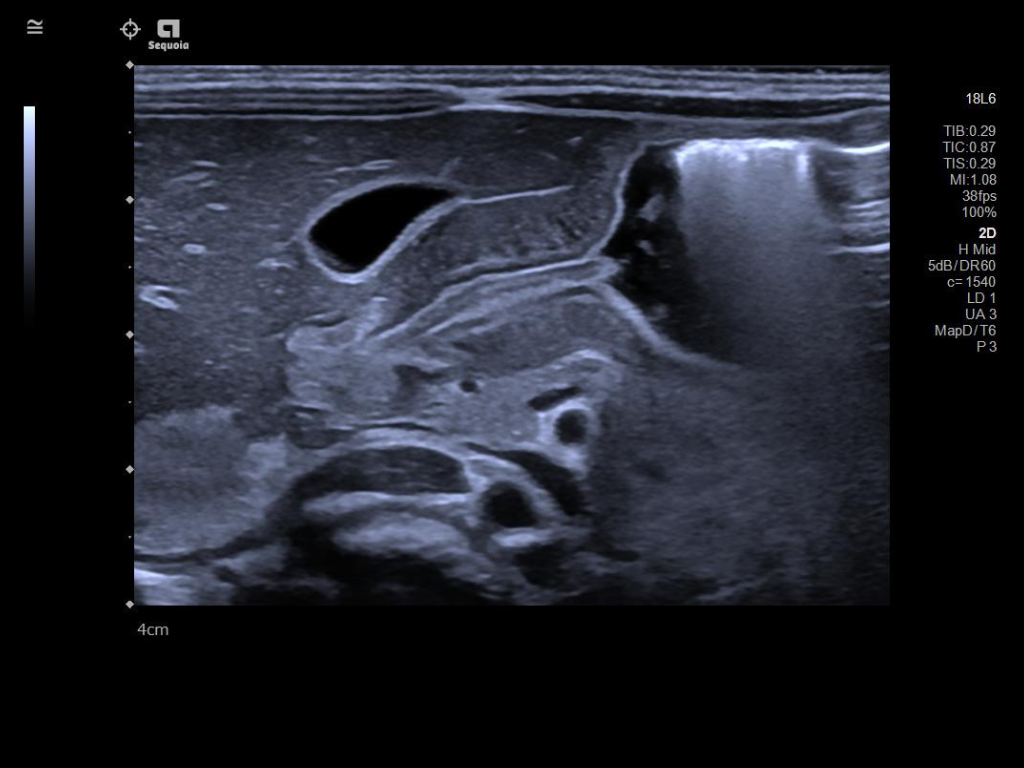

ACUSON Sequoia’s InFocus imaging architecture eliminates the need for conventional focal zones to create a fully focused image faster than conventional systems. Our InFocus technology applies to all imaging transducers and exam types giving you consistent imaging across clinical segments. Some of the benefits are:

- Image uniformity throughout the field of view

- Aesthetically pleasing speckle

- Improved spatial and contrast resolution

- Clear near field to far field

- High resolution imaging at high frame rates